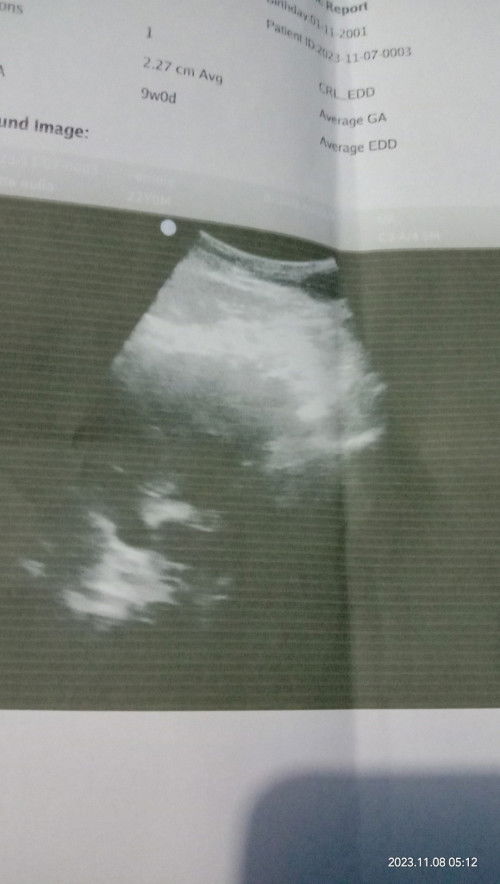

Aku kemarin 5w baru kelihatan kantongnya aja bun, 1 bulan lagi disuruh usg buat lihat pertumbuhan janin

SMA Bun kemaren jg gitu sya Bun. ini ntar bulan depan suruh USG lagi

iya bunda sama , kata dokter nya blm blm kelihatan

sama bun aku juga kemarin USG tpi belum kelihatan

sama buun saya usg 5w3d masih penebalan dinding rahim